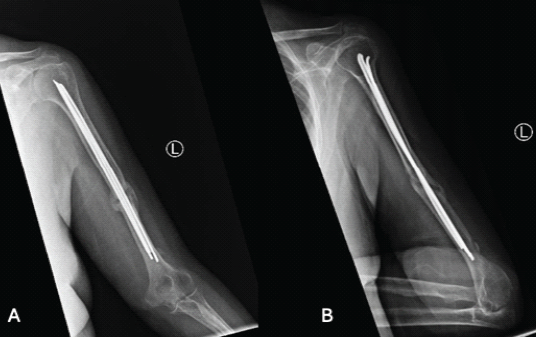

The patient was then seen in the office at 3-months postoperatively and reported significant improvement in pain, her elbow range of motion was 0–135° (Fig. 4).

Figure 4: (a) Anterior-posterior AP X-ray of the humerus 3 months postoperatively, (b) Lateral X-ray of the humerus 3 months postoperatively.

At 6-months post-operative follow-up, the patient was pain free with full range of motion, and radiographs demonstrated appropriate callus formation (Fig. 5).

Figure 5: (a and b) show anterior-posterior X-ray of the humerus 6 months postoperatively.